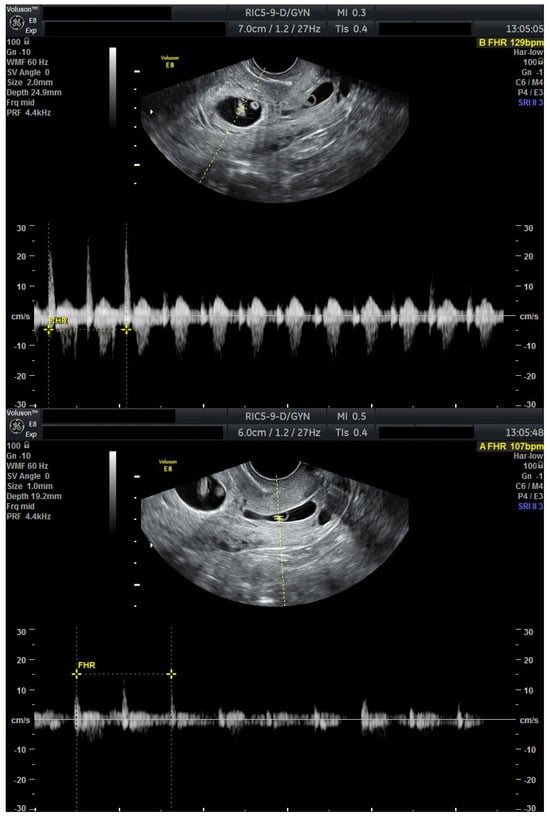

We present a personal case from our tertiary center in western Romania as an example of applicable findings from this review. A 32-year-old woman presented to the Municipal Clinical Emergency Hospital of Timișoara with first-trimester vaginal bleeding. Transvaginal ultrasound revealed a viable intrauterine gestation with a seven-week-old embryo with positive cardiac activity, as well as a simultaneous viable CP, confirming the diagnosis of HCP (Figure 1).

Figure 1.

Ultrasound evaluation at diagnosis with viable heterotopic embryos (Day 0). Combined ultrasound of both gestational sacs. Transvaginal ultrasound evaluation: sagittal view through the uterus and cervical canal. FHR present in both embryos. Patient information is anonymized.

The patient first received mifepristone 200 mg orally at time of diagnosis (Day 0). At 48 h, repeat ultrasound demonstrated persistent cardiac activity in both the intrauterine and cervical gestations.